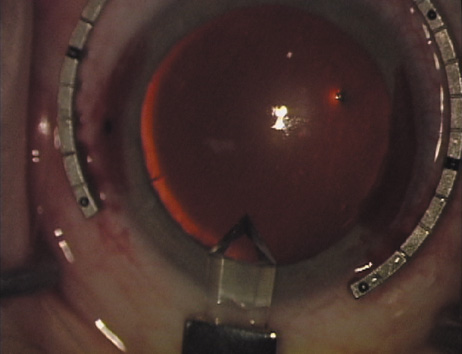

markers, rings, and blades for performing LRIs.  Fig. 4. The Nichamin Fixation Ring and Gauge serves to both fixate the globe and

delineate the extent of arc to be incised; a two-cut radial marker may

be used to mark the extent of arc to be incised, and the Mastel Nichamin

Force AK Diamond Blade with preset depth of 600 microns. Fig. 4. The Nichamin Fixation Ring and Gauge serves to both fixate the globe and

delineate the extent of arc to be incised; a two-cut radial marker may

be used to mark the extent of arc to be incised, and the Mastel Nichamin

Force AK Diamond Blade with preset depth of 600 microns.

|